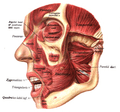

Muscles of the head, face, and neck. (Nasalis labeled at center left.) | |